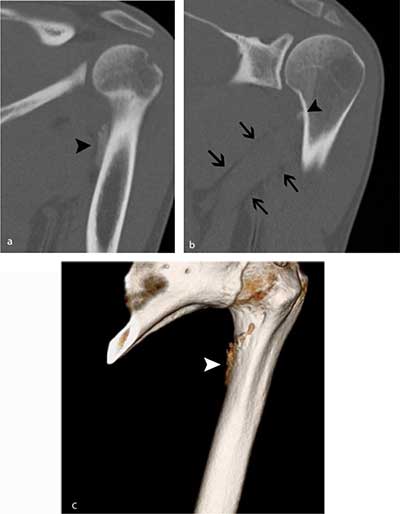

Figure 4

Follow-up CT five weeks later. a) Oblique coronal reformatted image of the proximal humerus shows a slightly more dense aspect of the periphery of the calcification (black arrowhead). b) MIP reconstructions (1.5 mm) clearly show that the calcification is located at the medial crest of the lesser tuberosity (black arrowhead). Note also the perimuscular fat pads surrounding the teres major muscle (black arrows). c) Volume Rendering Technique (VRT) image revealing irregular contour (white arrowhead) near the medial crest of the lesser tuberosity.

The spiral course of the teres major generates rotational forces (Figure 6) [3]. As a consequence, trauma may result in a broad-based periosteal stripping lesion, which will curl up and progressively calcify during the follow-up of the lesion. The mechanism is comparable with medial femoral epicondylar periosteal stripping in Pelligrini-Stieda or with periosteal stripping occurring in common adductor insertion avulsion of the thigh (thigh splint) [45]. Due to its close anatomical relationship with the tendinous insertion of the latissimus dorsi, an avulsion fracture of both tendons may co-exist (Figure 6) [6]. Teres major tears are predominantly seen on imaging at the distal musculotendinous junction (MTJ). Generally, MTJ lesions are divided in three grades. A grade 1 tear shows feathery edema around the MTJ. A partial disruption is categorized as grade 2 lesion whilst a complete disruption is a grade 3 lesion [7]. Imaging findings of a tear at the tendon bone insertion has – to the best of our knowledge – not been reported yet.

Standard radiography in the acute phase may reveal a small subtle fleck of bone at the periosteal insertion of the teres major. This should not be misinterpreted as a bony Bankart lesion, as the lesion is located slightly more inferiorly. CT may be useful to diagnose a subtle avulsion and for follow-up showing progressive peripheral calcification and ossification and ultimately fusion with the underlying cortex [4]. Although MR (arthrography) is currently a routine imaging tool for evaluation of shoulder trauma in sports trauma, it is important to analyze the images beyond the margin of the joint and scrutinize for extra-articular lesions [8]. Therefore, at least one imaging sequence with a large field of view should be used.